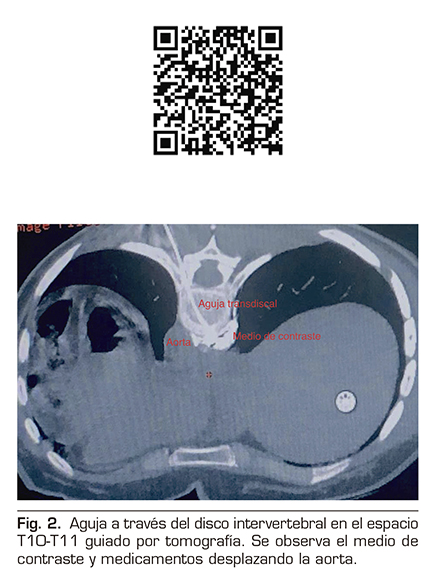

Se realizó un abordaje transdiscal de los nervios esplácnicos a nivel de T10-T11 guiado por tomografía.

Con la paciente en decúbito prono se identificó el espacio seleccionado, se infiltró lidocaína al 1 % a 5 cm de la línea media izquierda y se avanzó una aguja espinal número 22 progresivamente, realizando cortes topográficos hasta alcanzar el retromediastino. Se confirmó la punta de la aguja con 2 ml de medio de contraste iopromida 300 mg/ml (Ultravist®), y se procedió a inyectar bupivacaína 0,5 % más metilprednisolona 80 mg para un total de 10 ml (Figura 2).

Se dio por terminado procedimiento sin accidentes ni incidentes.